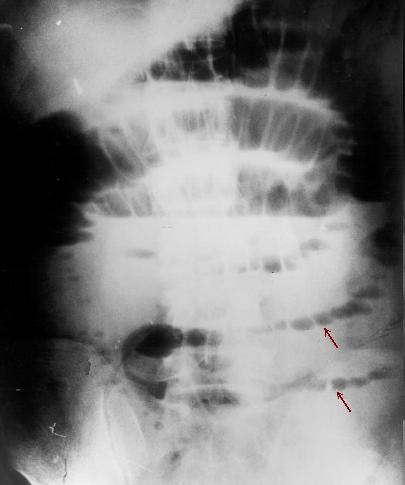

| Aspect radiologique ASP

de occlusion intestinal : Image hydro-arerique

des anses de l' intestin dilate et isolee au milieu de

l'abdomen . Les plies muqueuse de l'intestin sont

multiple et image de vide en aval de l'obstacle (

n'as pas image de air dans la region pelvienne ) |

Image en escalier typique de

occlusion de l'intestin grele . L'intestin est tres

dilate depasse 36mm de diametre et les niveaux hydrique se situe en

escalier

au milieu de l'abdomen . |